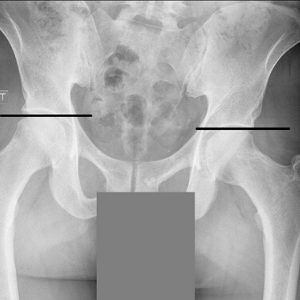

A key source of low back pain can be attributed to the sacroiliac joint, commonly referred to as the SI joint. The SI joint can be easily located behind the dimples in a person’s lower back on each side of your spine. The SI joint is where your sacrum connects to your pelvis.

At times, x-rays, MRIs, or scans might be necessary to further evaluate the affected region. While these may not always be necessary with every patient, they do show signs of injuries that might have occurred and if they have healed properly. This is extremely useful when there is a past medical history of trauma or impact to the SI joints, low back, or hips.